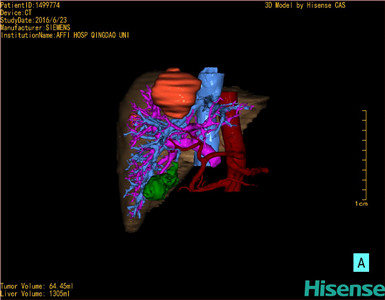

将0.625mm双源薄层CT资料的静脉期和动脉期Dicom格式文件导入海信CAS系统。

通过调节窗宽窗位调整CT序号,对肿瘤,肝实质,胆囊,下腔静脉,肿瘤,肝动脉、门静脉及肝静脉等进行三维重建;系统自动计算肿瘤体积和肝脏体积。

模拟手术操作,自动计算切除肿瘤体积。肝脏体积为1336ml,肿瘤体积为149.3ml,肿瘤体积为肝脏体积的11.2%,通过比对50-60岁正常肝脏体积为1330.41±329.13 ml,通过术前模拟手术,精准判断切除后剩余肝脏体积能耐受,避免肝衰竭发生。

术前手术方案的规划。

术前三维重建:重建图片